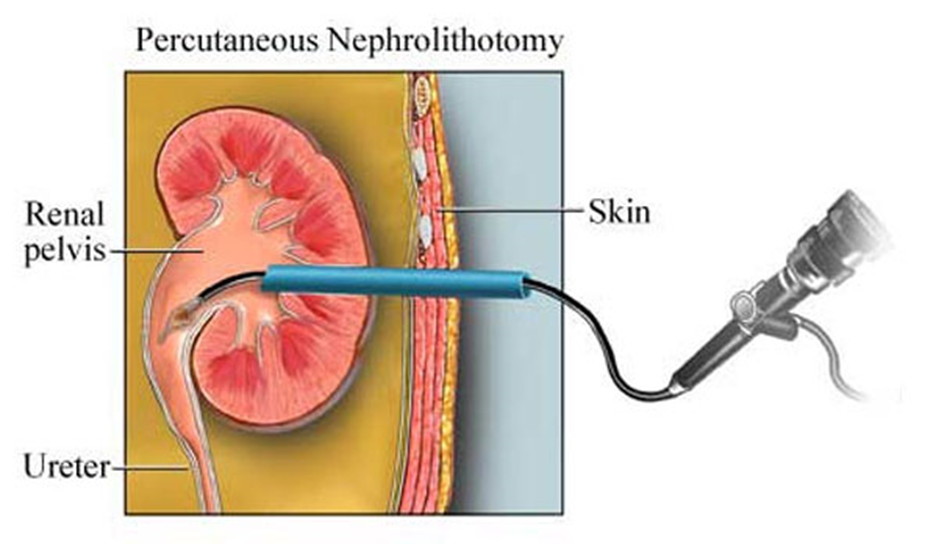

2 – La néphrolithotomie percutanée (NLPC)

Est une chirurgie mini-invasive utilisée pour retirer de gros calculs rénaux (souvent > 2 cm) en passant par une petite incision dans le dos. Elle consiste à insérer un néphroscope (un tube avec une caméra) dans le rein pour localiser, fragmenter et enlever le calcul. Cette intervention nécessite généralement une anesthésie générale et une courte hospitalisation de un à deux jours.